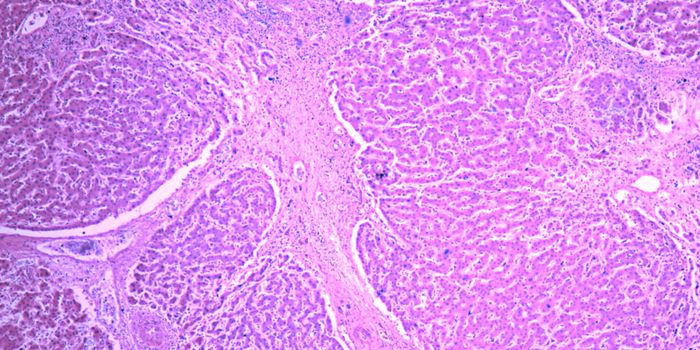

MAR 04, 2019Health & MedicineSarcoidosis is a rare, granulomatous disease that is found in the lungs of 90% of people diagnosed, but it can affect an ...